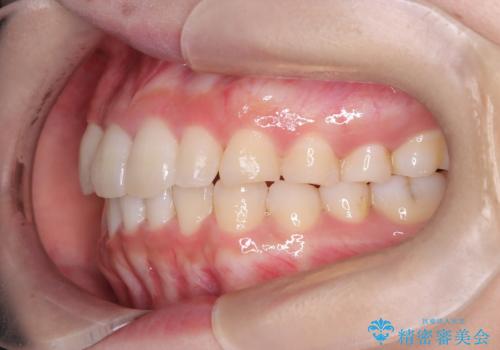

【インビザライン】八重歯が気になる

- 乳歯を抜歯してスペースを確保し八重歯の改善を行いました。

インビザラインをしっかり使用していただいたので、きれいな歯並びになりました。